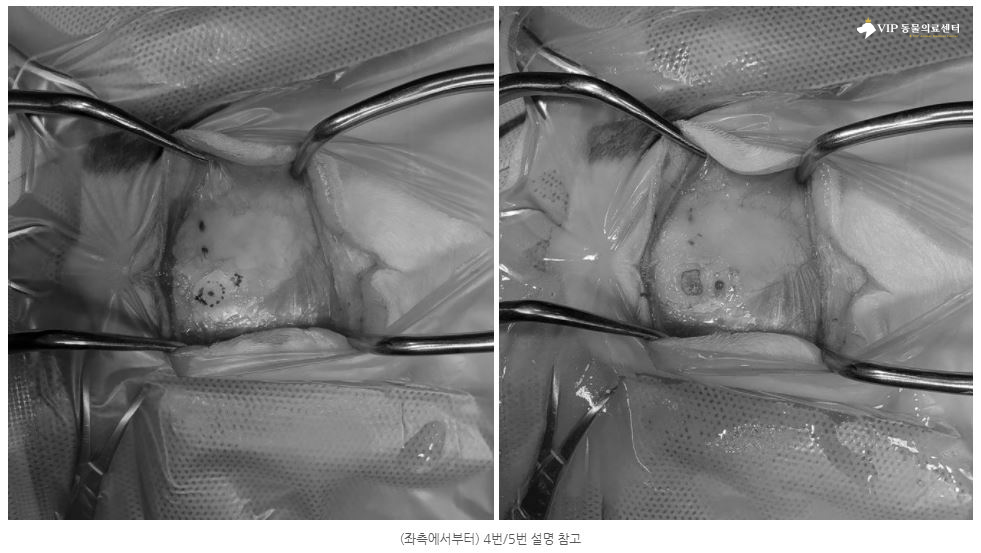

④⑤ 다음으로 머리 피부를 절개해 두개골을 노출시키고, 관을 뇌실로 정확히 삽입하기 위해 미리 계산해 둔 위치를 표시(이미지에 보시면 표시한 부분이 확인됩니다.)한 후, 뼈 절삭기를 이용해 두개골에 구멍을 냅니다.

⑥ 두개골에 만든 구멍을 통해 뇌 안으로 관을 넣어서 뇌척수액이 흘러나오는지 확인한 후 봉합사를 이용해 관을 두개골에 단단히 고정합니다.